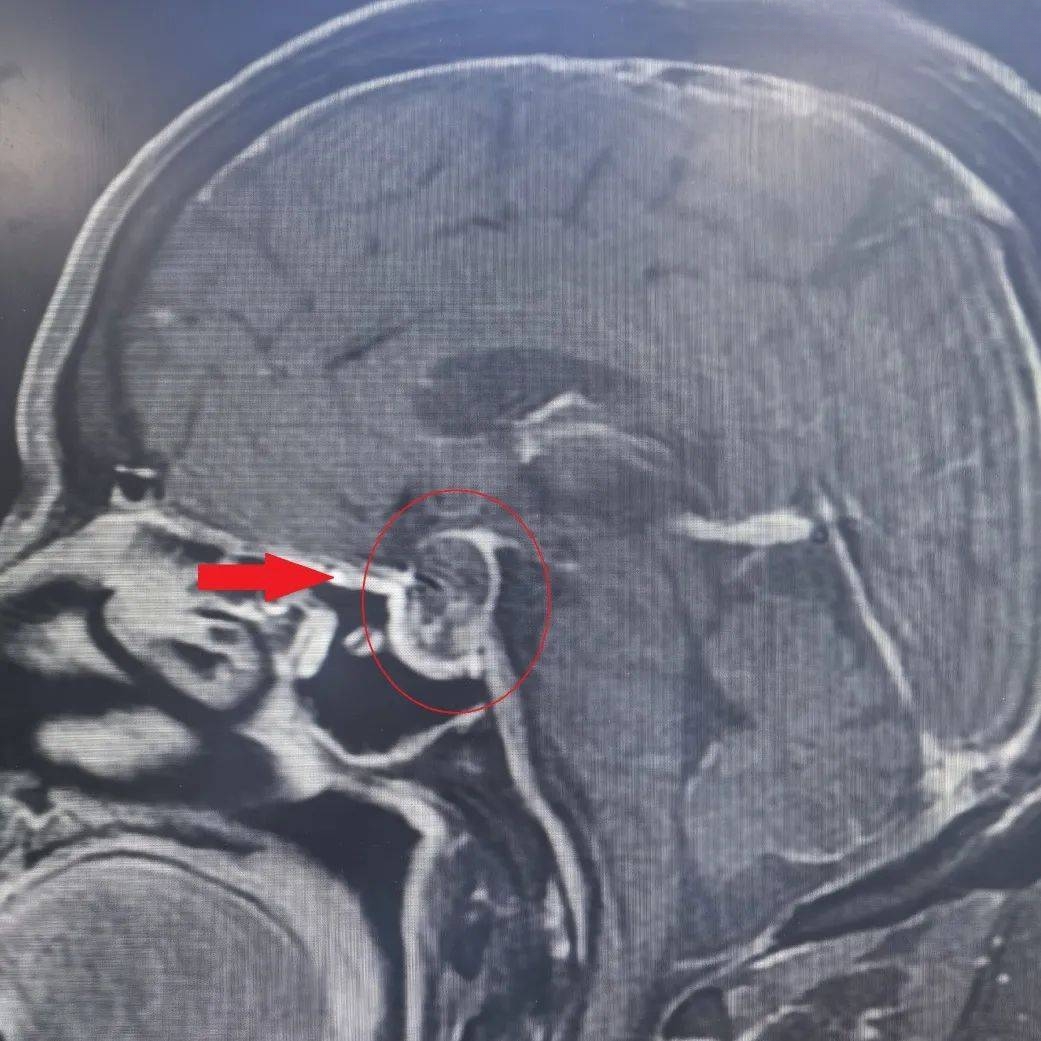

西安医学院一附院多学科联合救治一例复杂垂体瘤卒中患者